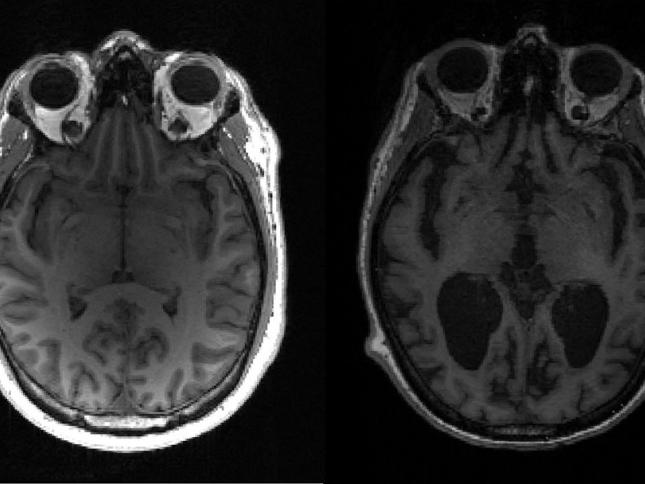

صحة اكتشاف سيغير علاجات ألزهايمر الدراسة هي الأولى التي تستخدم معطيات بشرية لتقييم سرعة التطوّرات الجزيئية التي تؤدّي إلى هذا المرض